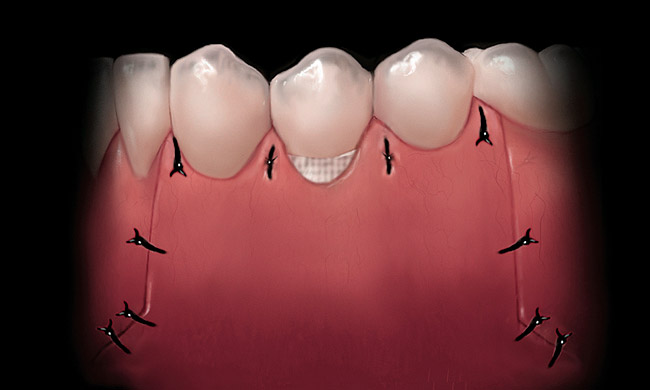

A local anesthetic should be administered mesially and distally of the intended surgical site. A sulcular incision is then started one tooth distal to the tooth/teeth to be treated. The incision is continued to the opposing side one tooth from the site requiring treatment. The papilla should be spared and left attached to the lingual soft tissue to help eliminate soft tissue loss interproximally. Vertical releasing incisions are next made bilaterally and carried beyond the mucogingival junction, ending in Burrow’s triangles (Figure 1). A Burrow’s triangle is used to relieve tension at the most apical extent of a vertical releasing incision to improve flap mobility and achieve tension-free closure.9

Figure 1  Incisions illustrated with Burrow’s triangles located apical to the mucogingival junction.

Figure 1